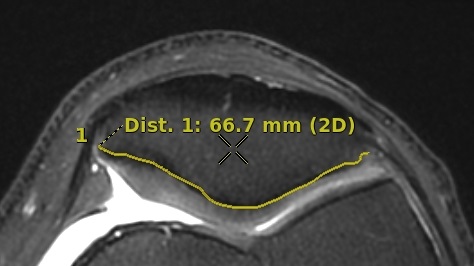

Figure 1. Example of an ROI identification number